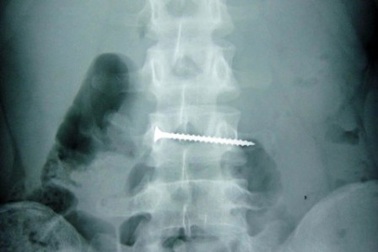

Nuốt đinh vít, bé 2 tuổi tử vongNhập viện trong tình trạng tím tái ngưng tim ngưng thở, X-quang cho thấy cây đinh vít nằm ở góc phế quản khiến phổi trái bệnh nhân gần như xẹp hoàn toàn. Dù bác sĩ đã tận tâm cứu chữa nhưng bệnh nhân không thể qua được nguy kịch.